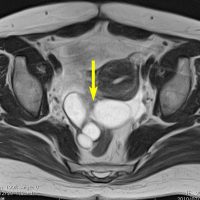

FSH産生腫瘍による卵巣過剰刺激症候群です。30代女性,数年間の月経不順の後で,両側の卵巣の多房性腫大 follicular cysts をきたしました。一度のう胞摘出を受けたのですが,のう胞性腫大が再燃して,FSHの軽度の上昇が疑われました。下垂体腺腫を全摘出したら卵巣のう胞は縮小して治りました。病理でFSHがびまん性に陽性なFSH産生腺腫の診断です。